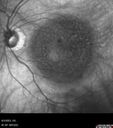

92 year old man The vision in the left eye has been declining for about 8 weeks. Prior to that the two eyes were similar. The left eye did have a prior retinal detachment. The RD was in the 1990's. It was repaired by Dr. Tom Ward. Dr. Cohen saw the patient afterward and did a lot of treatment for retinal tears. Medical Hx: BPH. Congestive Heart Failure. Hypertension, Systemic. Pure Hypercholesterolemia, Unspecified. Surgical Hx: Tonsillectomy. Appendectomy. Herniorrhaphy. Cataract Surgery. Systemic Meds: Avodart 0.5 mg. Calcium 500mg. Digitek 125mcg. Eliquis 5mg. Entresto 24mg. Lasix midodrine 5mg. Ocuvite. Propafenone 150mg. Vitamin D. Zocor 20mg. VA 20/25 OD, 20/200 OS IOP 8 OD, 12 OS

Wet AMD - Type 1 CNVM - RAP lesion85 views92 year old man with vision loss and very high PED. Because of worry about a PED tear, patient was treated with avastin, then lucentis, then eyelea, then vabysmo (progressively stronger meds)00000